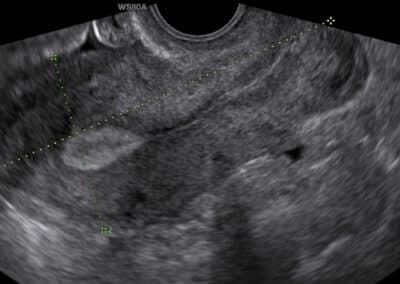

Ultrasound examination of the uterus